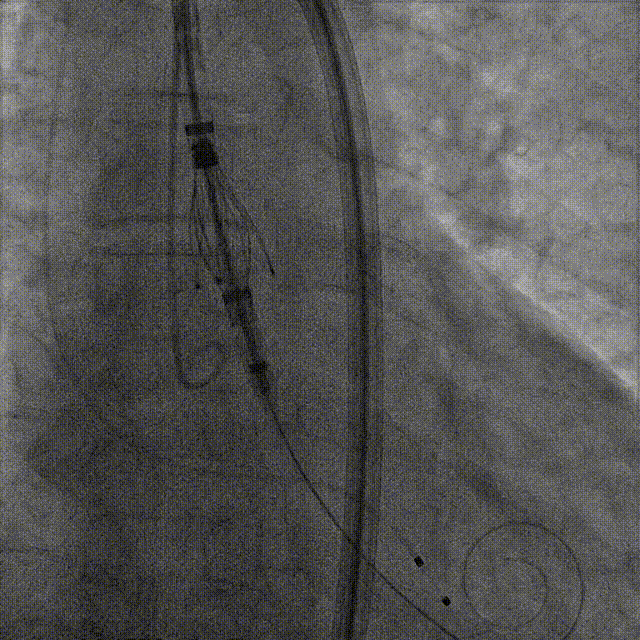

深度推进确认

起搏一键释放

术后造影